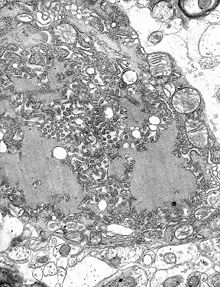

The rabies virus is the type species of the Lyssavirus genus, in the family Rhabdoviridae, order Mononegavirales. Lyssaviruses have helical symmetry, with a length of about 180 nm and a cross-section of about 75 nm. These viruses are enveloped and have a single-stranded RNA genome with negative sense. The genetic information is packed as a ribonucleoprotein complex in which RNA is tightly bound by the viral nucleoprotein. The RNA genome of the virus encodes five genes whose order is highly conserved: nucleoprotein (N), phosphoprotein (P), matrix protein (M), glycoprotein (G), and the viral RNA polymerase (L).

Once within a muscle or nerve cell, the virus undergoes replication. The trimeric spikes on the exterior of the membrane of the virus interact with a specific cell receptor, the most likely one being the acetylcholine receptor. The cellular membrane pinches in a procession known as pinocytosis and allows entry of the virus into the cell by way of an endosome. The virus then uses the acidic environment of that endosome and binds to its membrane simultaneously, releasing its five proteins and single strand RNA into the cytoplasm.

The L protein then transcribes five mRNA strands and a positive strand of RNA all from the original negative strand RNA using free nucleotides in the cytoplasm. These five mRNA strands are then translated into their corresponding proteins (P, L, N, G and M proteins) at free ribosomes in the cytoplasm. Some proteins require post-translative modifications. For example, the G protein travels through the rough endoplasmic reticulum, where it undergoes further folding, and is then transported to the Golgi apparatus, where a sugar group is added to it ( glycosylation).

Where there are enough proteins, the viral polymerase will begin to synthesize new negative strands of RNA from the template of the positive strand RNA. These negative strands will then form complexes with the N, P, L and M proteins and then travel to the inner membrane of the cell, where a G protein has embedded itself in the membrane. The G protein then coils around the N-P-L-M complex of proteins taking some of the host cell membrane with it, which will form the new outer envelope of the virus particle. The virus then buds from the cell.

From the point of entry, the virus is neurotropic, traveling quickly along the neural pathways into the central nervous system, and then to other organs. The salivary glands receive high concentrations of the virus, thus allowing further transmission.